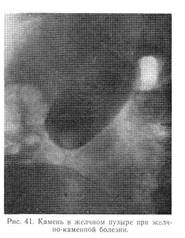

Рентгенологически (при контрастной холеграфии) обнаруживаются единичные или множественные камни (рис. 41). Реже тени конкрементов видны и на обзорной рентгенографии. Диагностическое значение в последнее время приобрела абдоминальная эхография.